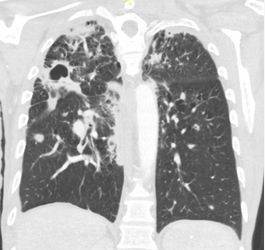

GPA granulomatosis with polyangitis CT chest shows cavitary diseases

- This patient has a chronic multiorgan system disease characterized by cavitary lung disease (GPA granulomatosis with polyangitis CT chest shows cavitary diseases), peripheral neuropathy, and brain and liver lesions. He has had an extensive workup for infectious and neoplastic diseases, which has been negative. The combination of chronic cavitary lung disease and peripheral neuropathy should raise the suspicion of systemic vasculitis, especially granulomatosis and polyangiitis (GPA). GPA is a necrotizing granulomatous vasculitis (granulomatosis with polyangiitis histology shows necrotizing granulomas) that predominantly affects small vessels of the upper respiratory tract, the lower respiratory tract, and the kidneys, although any organ can be involved.